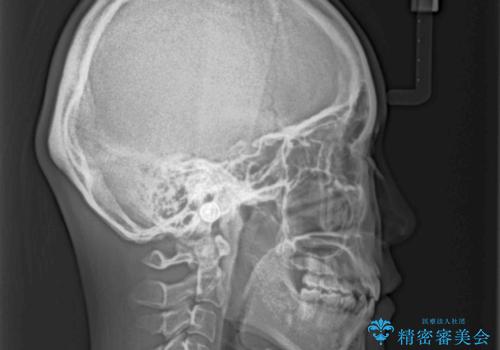

- 口元の突出感と口の閉じにくさ、前歯のデコボコを気にして来院された患者様です。

上下左右第一小臼歯4本を抜歯し、ワイヤー装置にて口元を引っ込めるよう矯正治療を行うこととしました。

骨格的に下顎骨が前方位にあるため、口元の突出感改善には限界があると思われましたが、唇の閉じにくさが改善するほど引っ込めることができました。